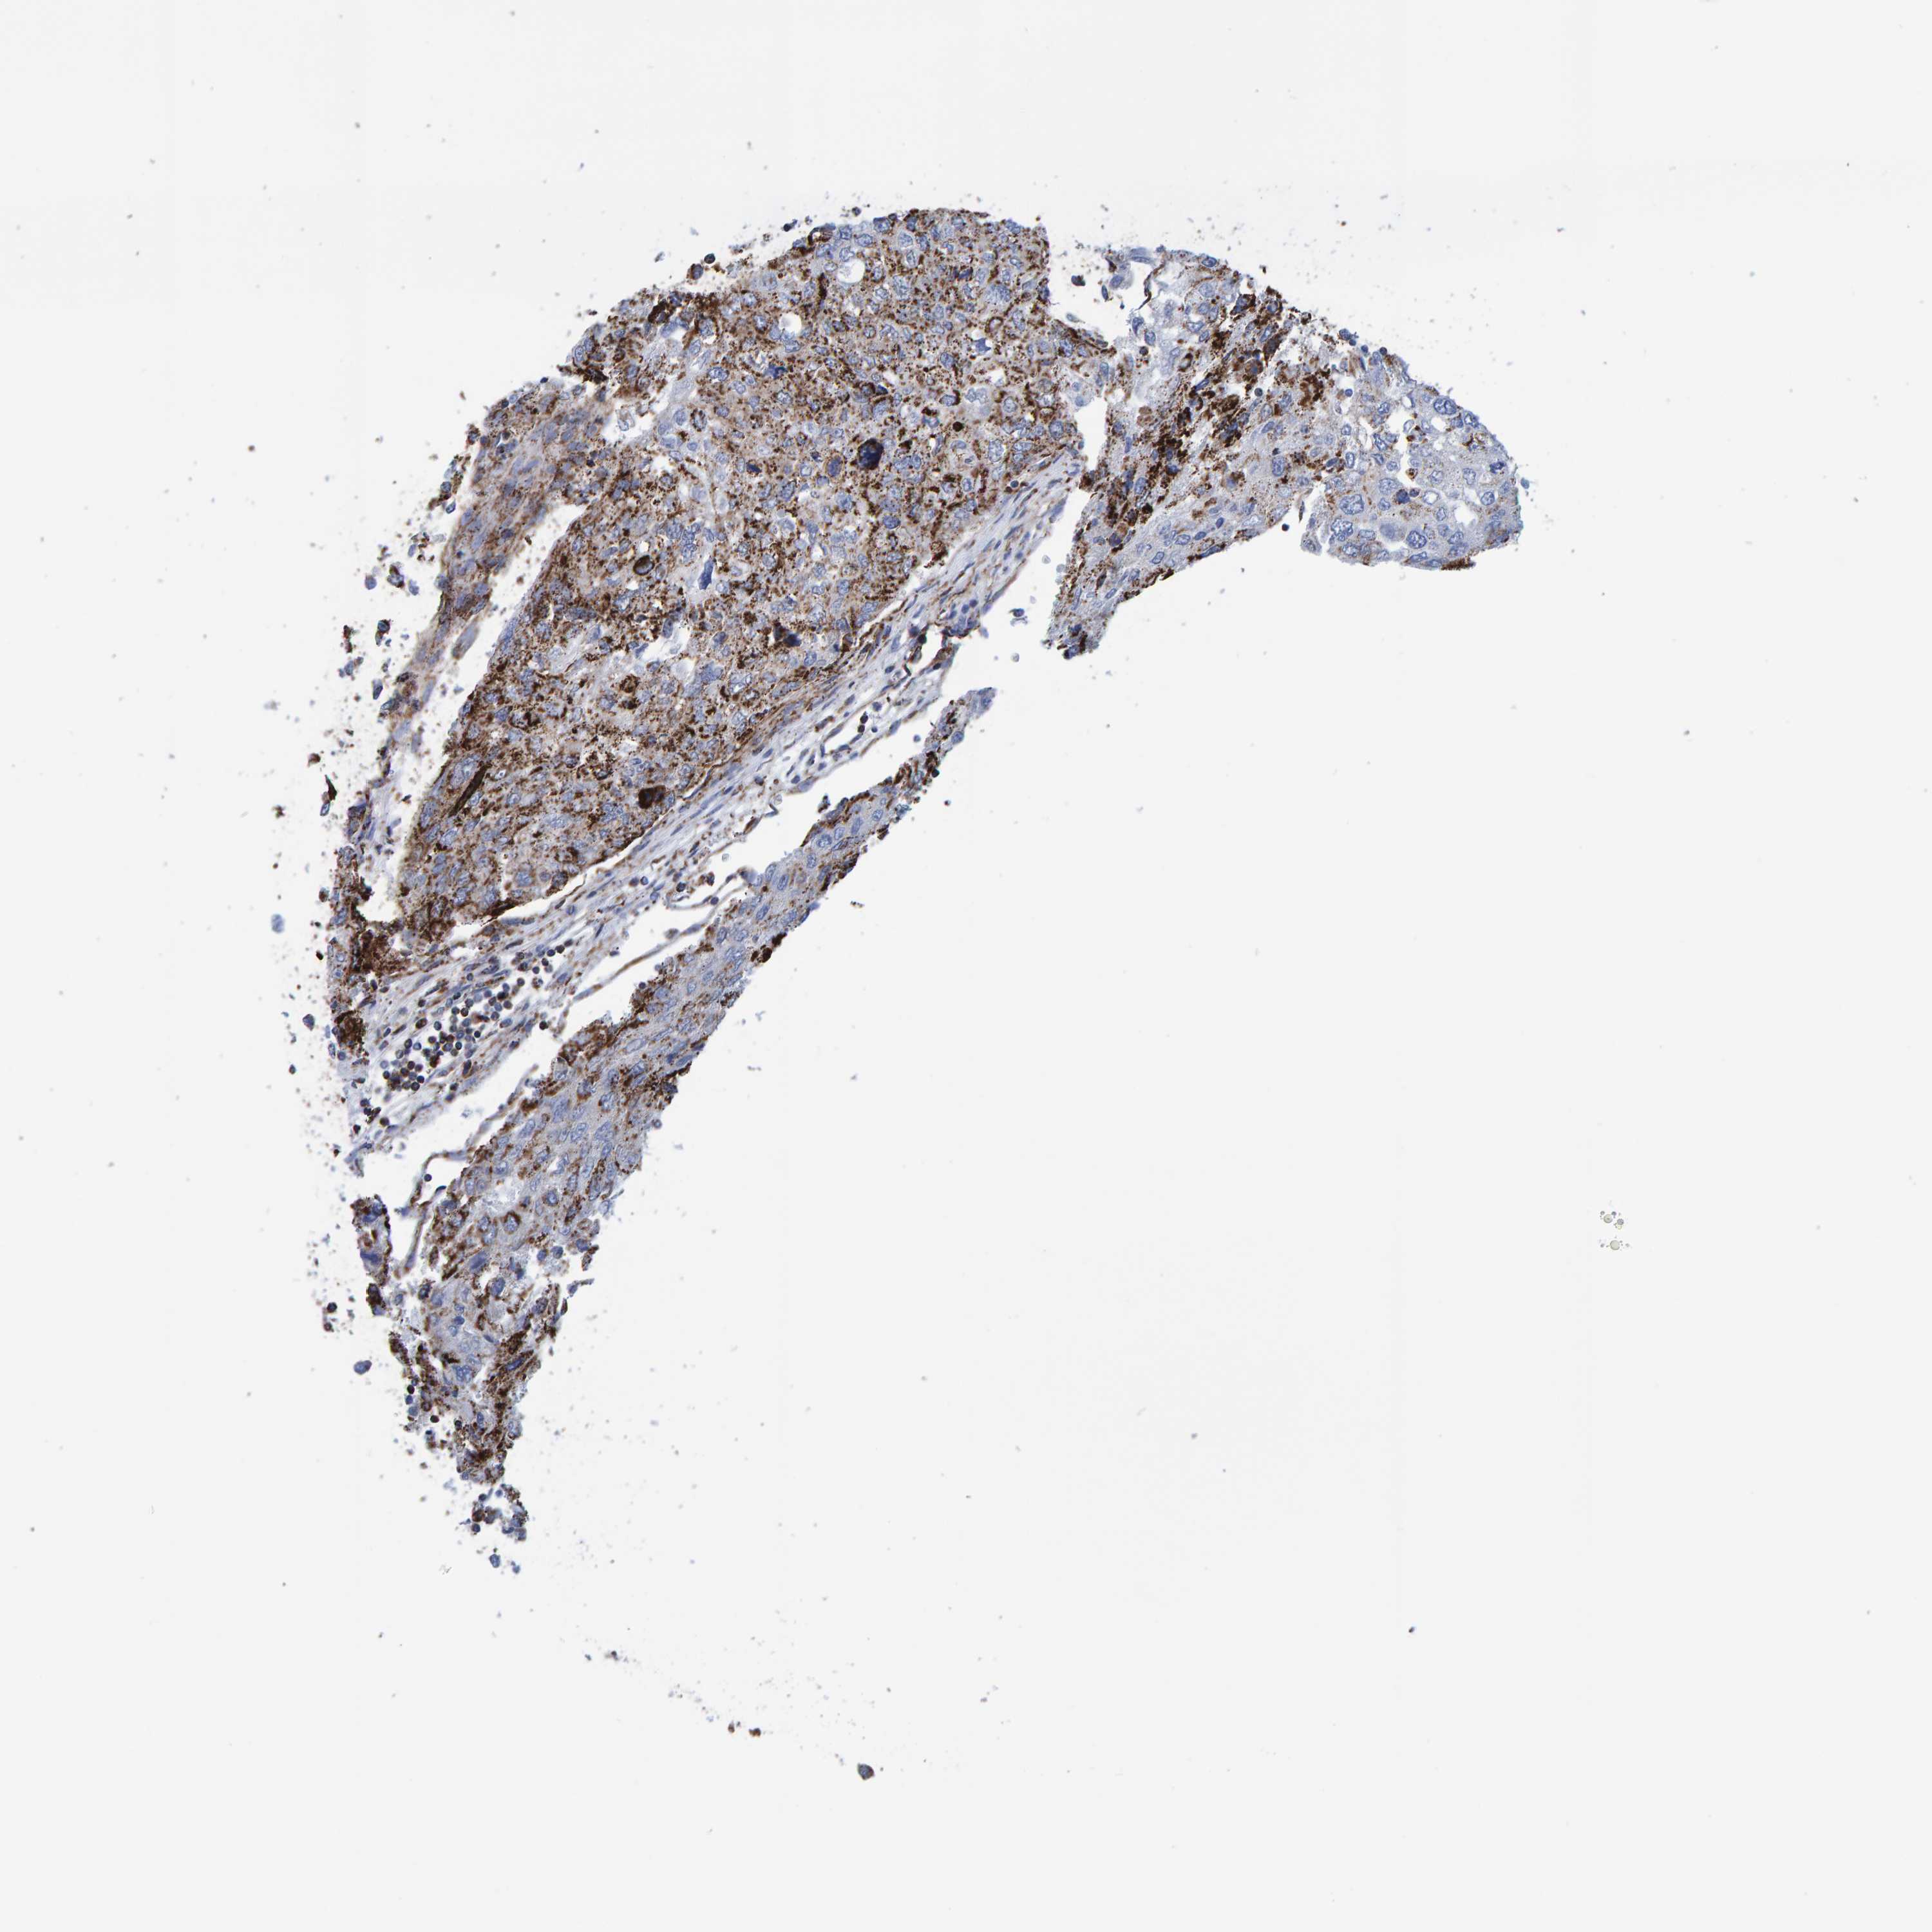

UROTHELIAL CANCER - Protein expressioni

A mouse-over function shows sample information and annotation data. Click on an image to view it in a full screen mode. Samples can be filtered based on level of antibody staining by selecting one or several of the following categories: high, medium, low and not detected. The assay and annotation is described here.

Note that samples used for immunohistochemistry by the Human Protein Atlas do not correspond to samples in the TCGA dataset.

Antibody stainingi

Antibody staining in the annotated cell types in the current human tissue is reported as not detected, low, medium, or high, based on conventional immunohistochemistry profiling in selected tissues. This score is based on the combination of the staining intensity and fraction of stained cells.

Each image is clickable and will lead to virtual microscopy that enables deeper exploration of all samples and also displays staining intensity scores, fraction scores and subcellular localization as well as patient and tissue information for each sample.

Antibody HPA022853

Antibody HPA023043

Antibody HPA023048

Staining

High

Medium

Low

Not detected

Intensity

Strong

Moderate

Weak

Negative

Quantity

>75%

75%-25%

<25%

None

Location

Nuclear

Cytoplasmic/membranous

Cytoplasmic/membranous,nuclear

Urothelial carcinoma, Low grade

Urothelial carcinoma, High grade